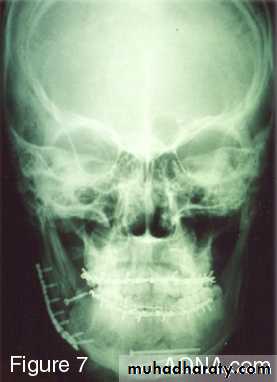

• Open reduction

• Intraosseous wiring + IMF (3 to 8 weeks)• Rigid internal fixation (plating) these method use bone plates, bone screws or both to fix the fracture.

Plating

If teeth are present IMF is done ; then incision is made and bone is reached either extra orally or intra orally.The fractured ends are approximated and screw holes are made such that at least 2 screws can be placed on either side of the fracture.

The champy,s technique of plate fixation

1- Use mono cortical screw fixation ; place a minimum of 2 screws on each side of the fracture.2- The more posterior the fracture the more higher the plate should be placed . The more anterior the fracture , the closer the plate should be placed to the lower border.

3-To avoid devitalization of bone , place plates supra periosteally in atrophic edentulous mandible and extensively comminuted fracture.

In plating posterior mandible single upper border plate is enough for fixation. While in plating anterior mandible , two plates are required to help counter the torsional forces of fracture in this location.